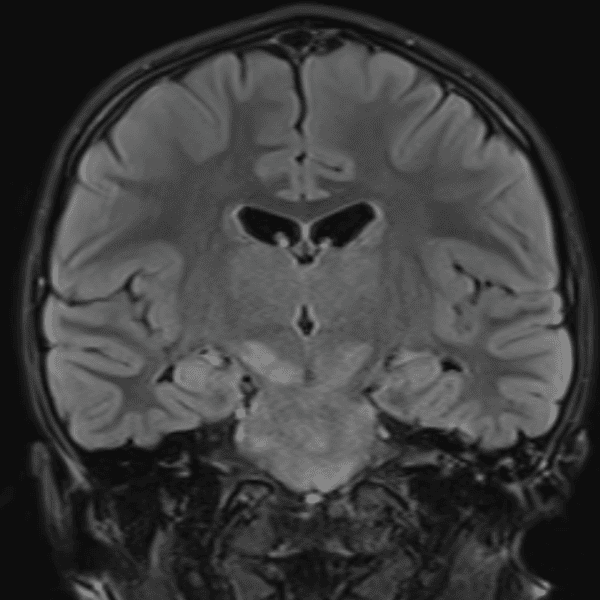

๋‹น์ง ์‹œ ํ”ํžˆ ๋ณผ ์ˆ˜ ์žˆ๋Š” ์‚ฌ๋ก€์˜ ์ „ํ˜•์ ์ธ ์˜ˆ๋ฅผ ํฌํ•จํ•ฉ๋‹ˆ๋‹ค.

39 ์‚ฌ๋ก€

์—ฐ์Šต

๋ฏธ๋ฌ˜ํ•˜๊ฑฐ๋‚˜ ์–ด๋ ค์šด ์‚ฌ๋ก€์™€ ์ผ๋ถ€ ์ •์ƒ ์‚ฌ๋ก€๋ฅผ ํฌํ•จํ•˜์—ฌ ๋‹น์ง์„ ์‹œ๋ฎฌ๋ ˆ์ด์…˜ํ•ฉ๋‹ˆ๋‹ค.

50 ์‚ฌ๋ก€